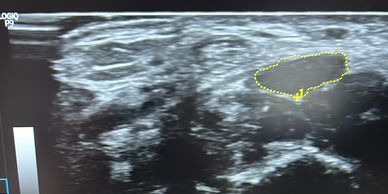

Neuromuscular Ultrasound